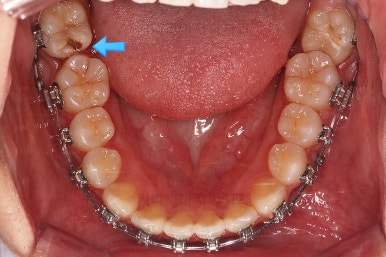

점점 뒤쪽 치아가 바로 일으켜세워지고 있네요.

생각보다 많이 썩은 상태였어요.

앞쪽 치아 하방으로 갇혀 있으면서 훨씬 심각한 상태까지 충치가 진행되었던거죠.

우측 상단에 보이던 어금니도 바로 세운 뒤, 치료를 했습니다.(골드 인레이)

왼쪽 상단으로 보이던 치아도 치료를 했어요.

좌우의 치아가 재료가 차이가 나는데 한 쪽은 튼튼하고 오래 쓸 수 있고 광범위한 부위에 맞는 인레이라는 치료방법 입니다.

왼쪽 치아도 인레이가 추천되는 상황이었지만 경제적인 사정을 고려해서 일단은 건강보험이 적용되는 재료인 GI(지아이)라는 재료로 치료를 했슨비다. 성질이 약한 단점이 있어서 주기적인 체크가 굉장히 중요합니다.